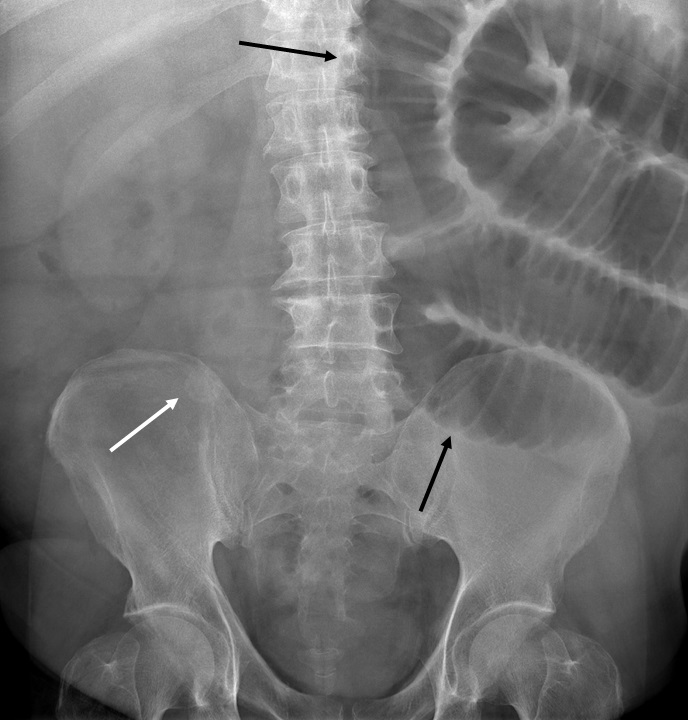

El divertículo de Meckel es la anomalía congénita más frecuente del tracto gastrointestinal, es un divertículo verdadero, ya que contiene todas las capas de la pared intestinal. Suele ser asintomático o se detecta de manera incidental en las pruebas de imágenes diagnósticas. Tiene un riesgo de complicación del 2-40%, siendo la más frecuentes la hemorragia, la obstrucción intestinal y la diverticulitis.

Se describe el caso de un paciente masculino de 52 años de edad, que consultó al servicio de urgencias del Hospital Universitario de Salamanca (España) por un cuadro de dolor abdominal, clínica infecciosa y  de obstrucción intestinal.

Mediante pruebas de imagen se diagnosticó una obstrucción intestinal secundaria a diverticulitis de Meckel por un enterolito, se realizó intervención quirúrgica y se confirmaron los hallazgos radiológicos descritos.